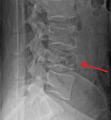

A burst fracture of L4 as seen on plane X ray

A burst fracture of L4 as seen one plane X ray